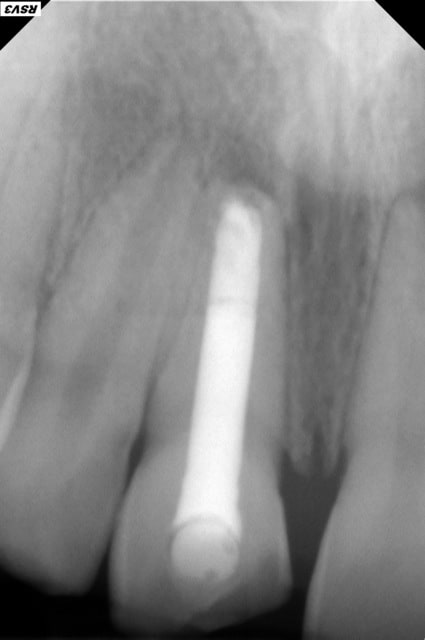

Autre cas avec petite modification dans le protocole pour éviter les mésaventures du cas précédent :

Adulte (dens in dente qui a entrainé la nécrose de la dent)

J'ai placé des éponges hémostatiques au delà de l'apex ce qui permet de créer un matelas plus dense à la limite de la racine et ainsi de condenser plus sereinement le MTA.

--